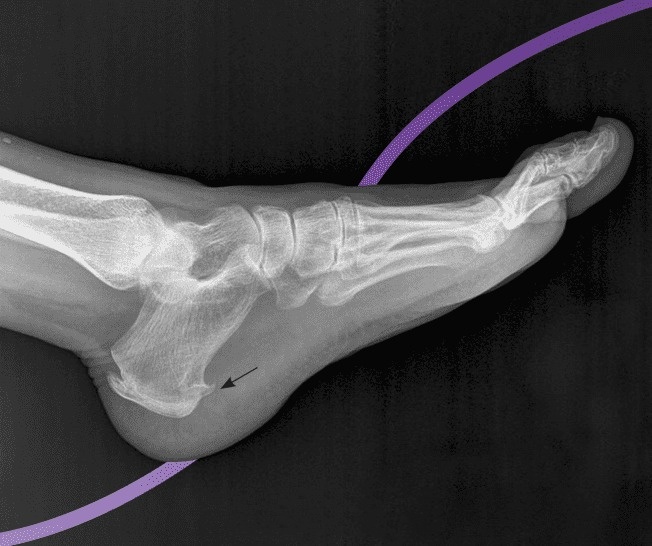

Na základě Anna životního stylu, chůze a rentgenových snímků jí tým Dr. Kevin Smith diagnostikoval kostní ostruhy a plantární fasciitidu. Kostní ostruhy dráždí okolní měkké tkáně, což způsobuje aseptický zánět. Kromě toho dlouhodobé nošení bot s tvrdou podrážkou a tlak vznikající při chůzi zhoršují opotřebení tukových polštářků, což vede k bolesti.